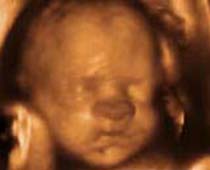

- Fetal Face Ultrasound Photos

- 3D Fetal Profile Ultrasound Scan Photos

- The Clinical Advantages of 3D and 4D Ultrasound

- Definition and Features of Four Dimensional Ultrasound

- Uses of 4D Ultrasound scan